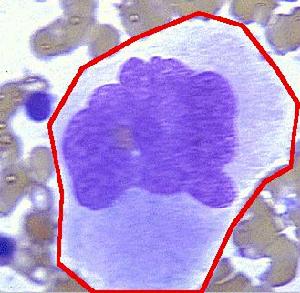

1.外周血 患者均有貧血的表現,為正細胞正色素性,1/3的患者血紅蛋白<60g/L,血細胞比容<0.2,血象中可見變形紅細胞及碎片者占95%,並可見球形紅細胞。有核紅細胞和網織紅細胞明顯增高(>30%),亦有報導先降低後升高者,中位值6.6%~19%。持續性血小板減少者92%,中位數(8~40.4)×109/L。白細胞增高者占60% 類白血病反應少見,但可有明顯左移,並可見幼稚粒細胞。

2.骨髓象 紅細胞系統顯著增生,巨核細胞數正常或增多,多數為幼稚巨核細胞,呈成熟障礙。

B.血片中破碎紅細胞>2%,偶見有核紅細胞。

①血小板計數常明顯降低,血片中可見巨大血小板。